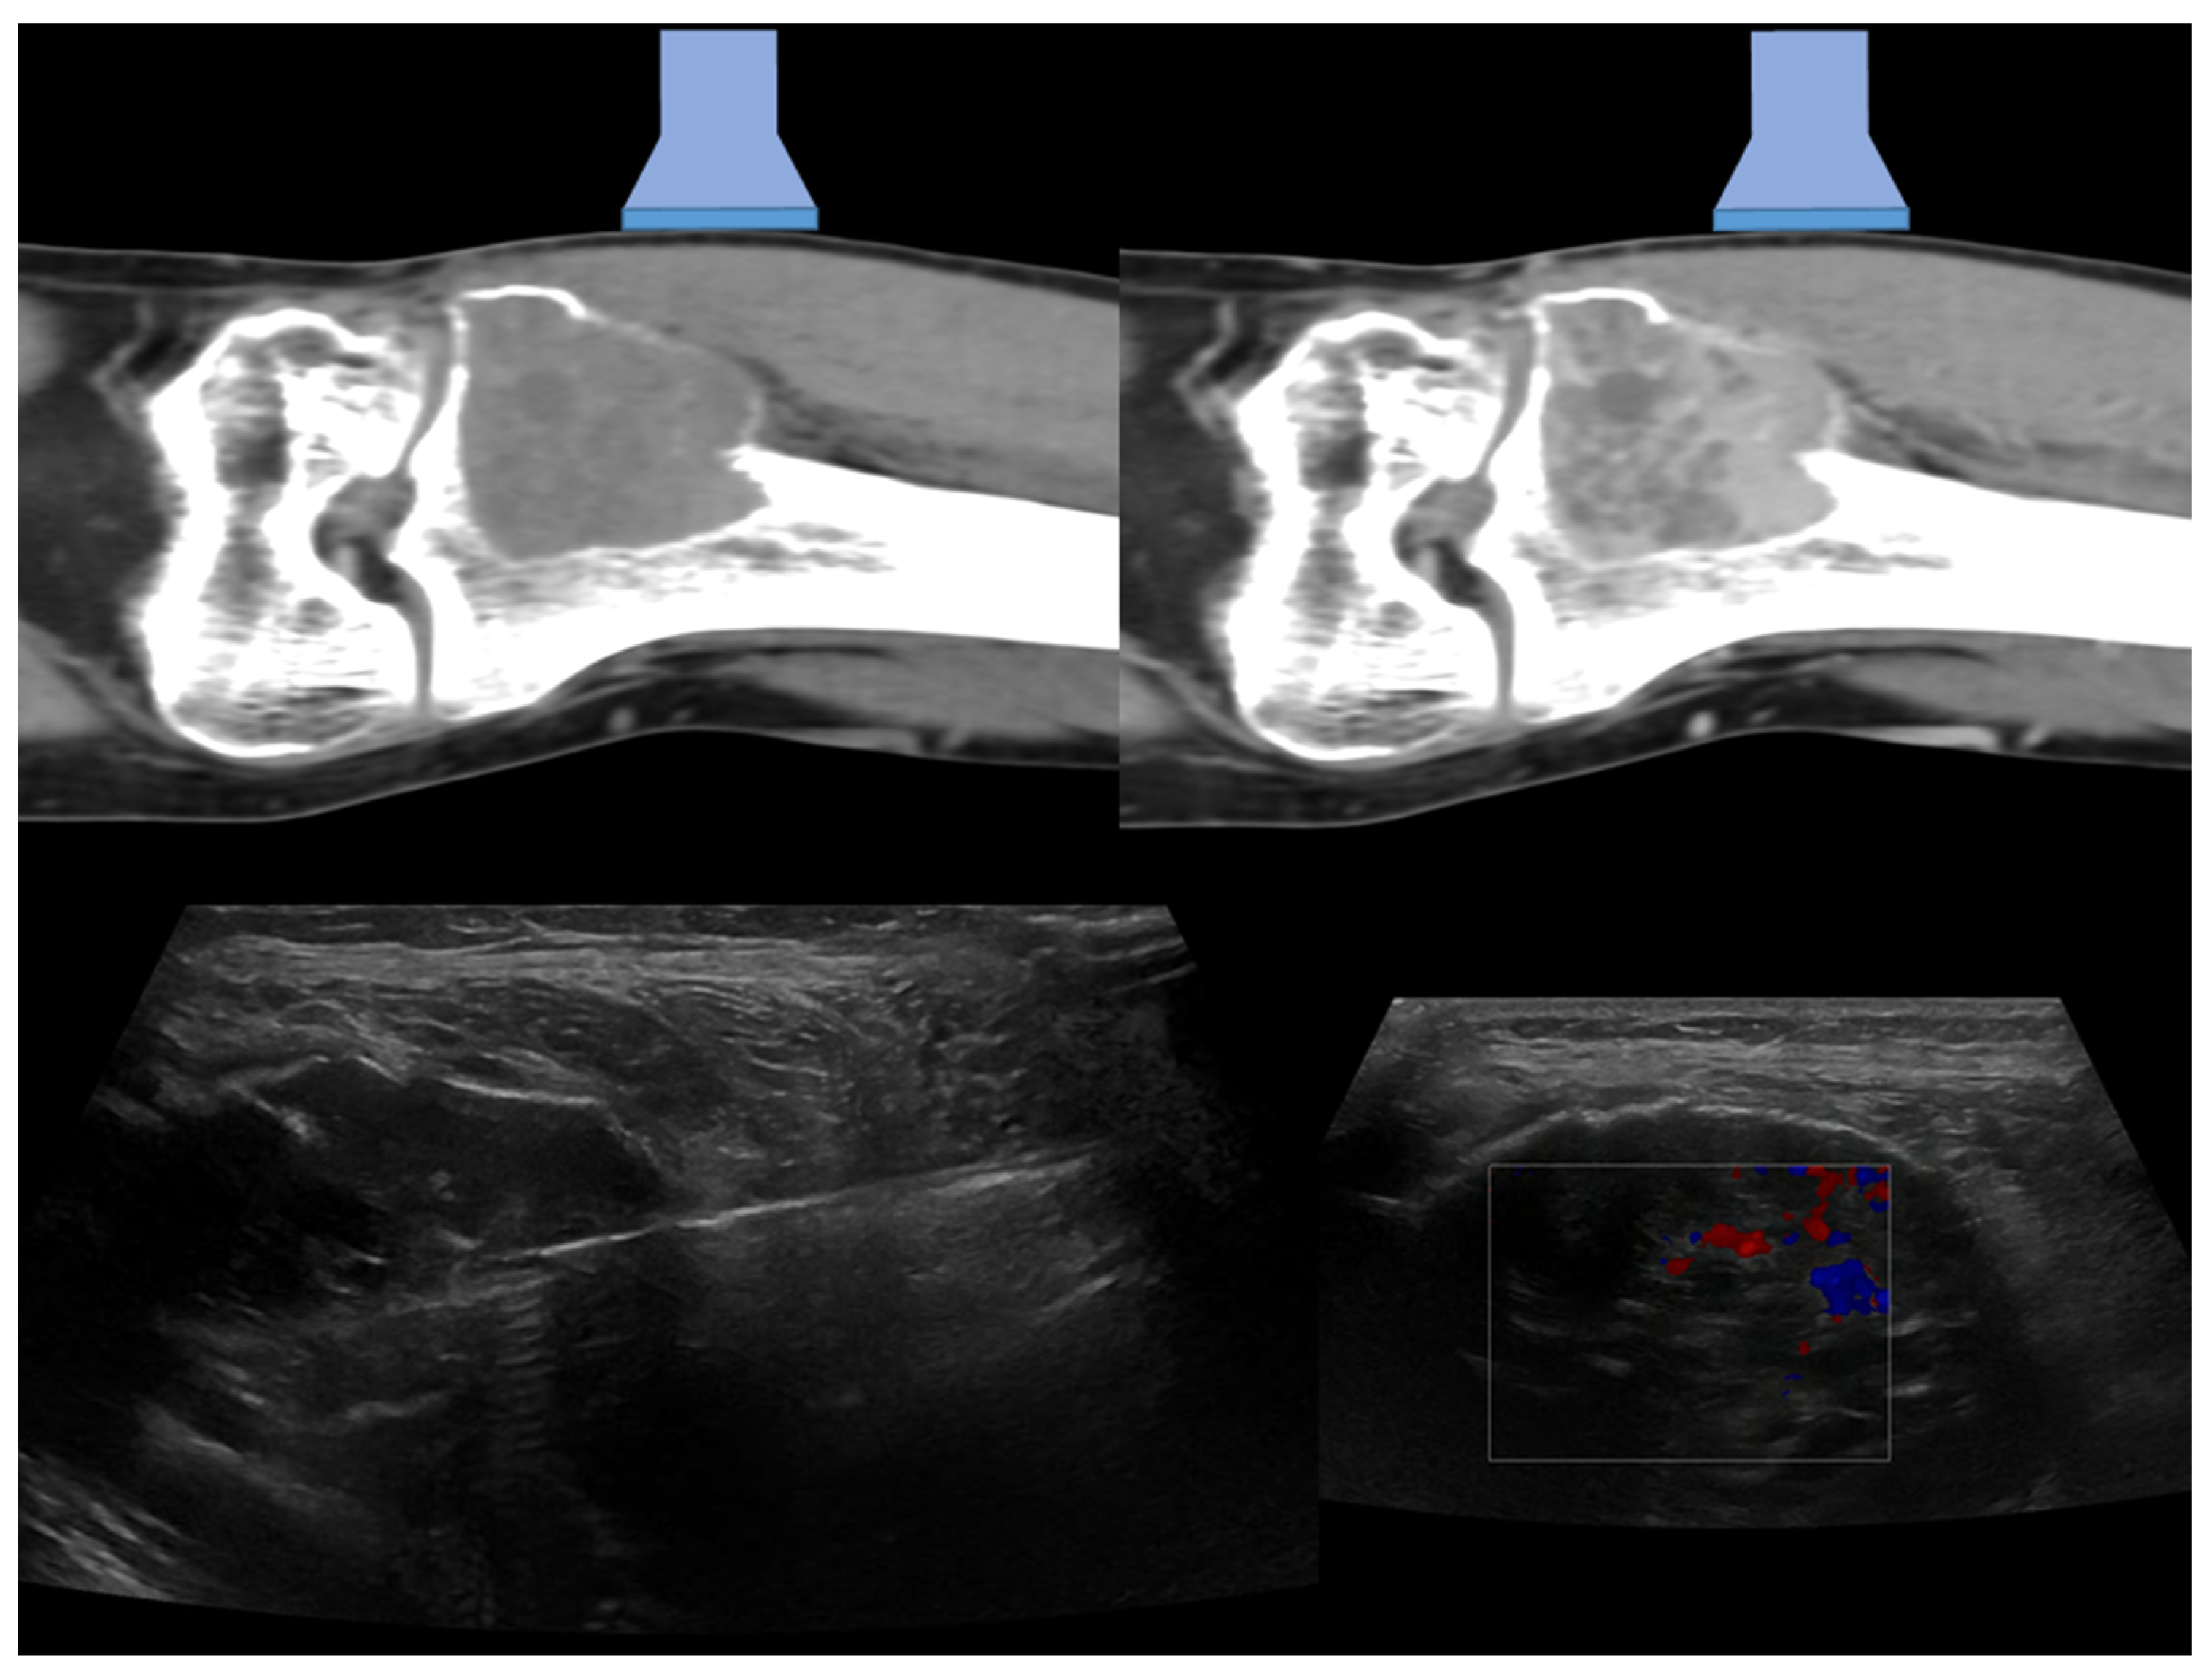

1.1. Percutaneous Bone Biopsy: General Indications

1.2. Imaging Guidance for Percutaneous Bone Biopsy

2. Technical Notes and Overview of Approaches

3.2.4. Target Lesion Location and Hybrid Techniques